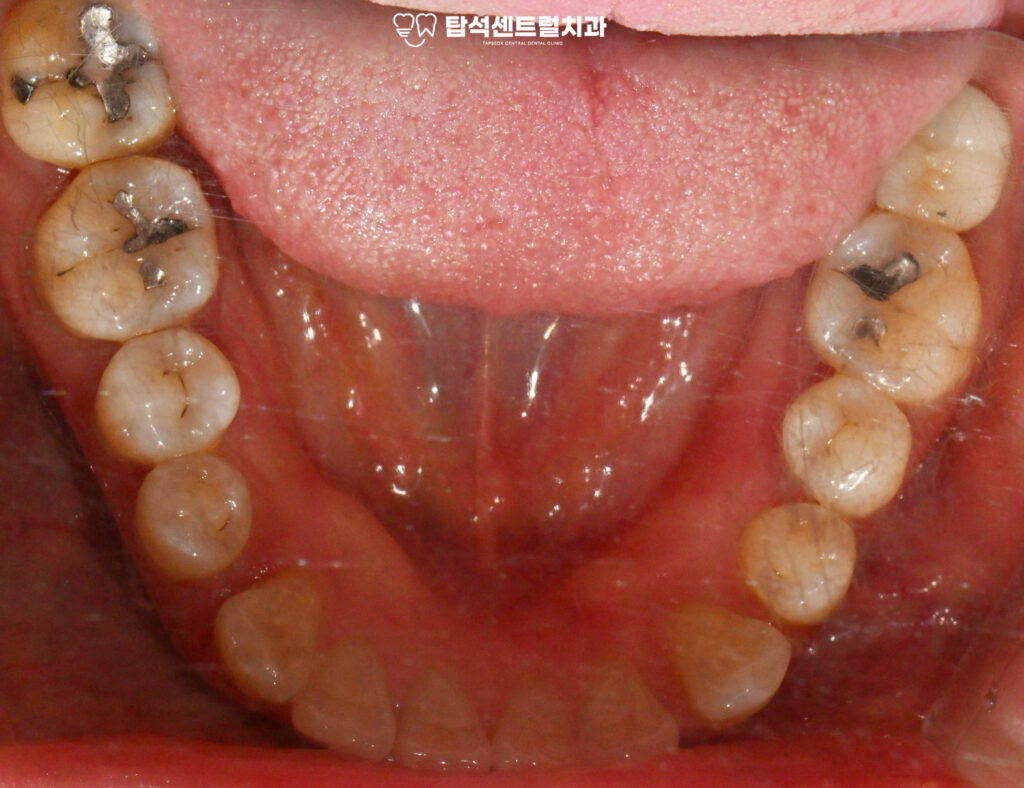

반면 아래턱 치아는 발치 즉시 식립이

가능한데, 이는 치조골 상태가 비교적

양호하고 초기 고정력을 확보할 수 있기 때문입니다.

아랫니 부위에 즉시 임플란트 식립과

발치와 보존술을 진행하기로 합니다.

당일 아랫니는 발거 후

픽스처를 심는 방식으로 진행됩니다.

즉시 식립은 발치와 식립을 한 번에 해결하여

치료 기간을 단축시킬 수 있다는 특징이 있습니다.

다만 뼈의 상태가 충분히 건강해야 하고

초기 안정성을 확보할 수 있어야 가능합니다.

이 기간 동안 10번과 40번대 사랑니 발치도

계획대로 진행되었고,

치경부 마모증 부위도 레진으로 수복하여

전반적인 구강 환경을 개선했습니다.

레진 수복을 통해 자연 치아색과 유사한 재료로

자연스러운 외관을 유지할 수 있었습니다.